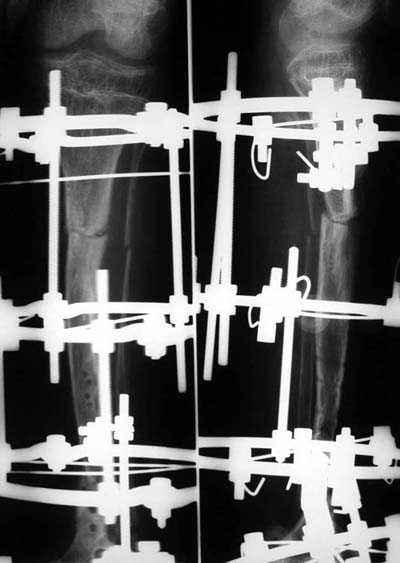

Уважаемые коллеги! В отделении на лечении наблюдается пациент 16 лет с диагнозом: Псевдоартроз костей левой голенив нижней трети. Вальгусная деформация обоих коленных суставов. Укорочение левой н/конечности11см. С 1997 года состоит на учёте у онколога с диагнозом: Рабдомиосаркома мышц тазового дна IV ст., с метастазами в метафизы берцовых костей.Проведена полихимиотерапия, лучевая терапия. В 1998 г. удаление опухоли. Послеоперационный период без особенностей. С 1998 года со стороны онкологии ремиссия, перестройка очагов метастазирования в берцовых костях по типу фиброзной дисплазии.В 1999 г. патологический перелом костей левой голени в н/трети. Лечение в гипсе 1.5 месяца, затем компрессионно-дистракционный остеосинтез апп. Илизарова. Сращения на месте псевдоартроза не достигнуто. С 1999г. ходит без нагрузки на левую н/конечность. Выраженный остеопороз костей н/конечностей. 17.11.05. Операция: Костная пластика зоны псевдоартроза левой б/берцовой кости по типу "русский замок", остеосинтез пластинкой и винтами. После начала нагрузки на конечность рецидив деформации, миграция фиксаторов. 05.12.06. Операция: Удаление фиксаторов из левой голени. Шарнирная остеотомия трети левой б/берцовой кости, остеотомия м/берцовой кости. Дистракционный остеосинтез апп. Илизарова. Устранены основные виды деформации б/берцовой кости. Планировали в дальнейшем несвободную костную аутопластику и интрамедуллярный остеосинтез с блокированием, но кость очень тонкая, склерозированная, выраженный остеопороз. Возникают большие сомнения о возможности сращения даже при этих условиях. Будем рады услышать ваши мнения по дальнейшему лечению данного пациента. Екатериан Анатольевна Озерова, детское отделение УНИИТО